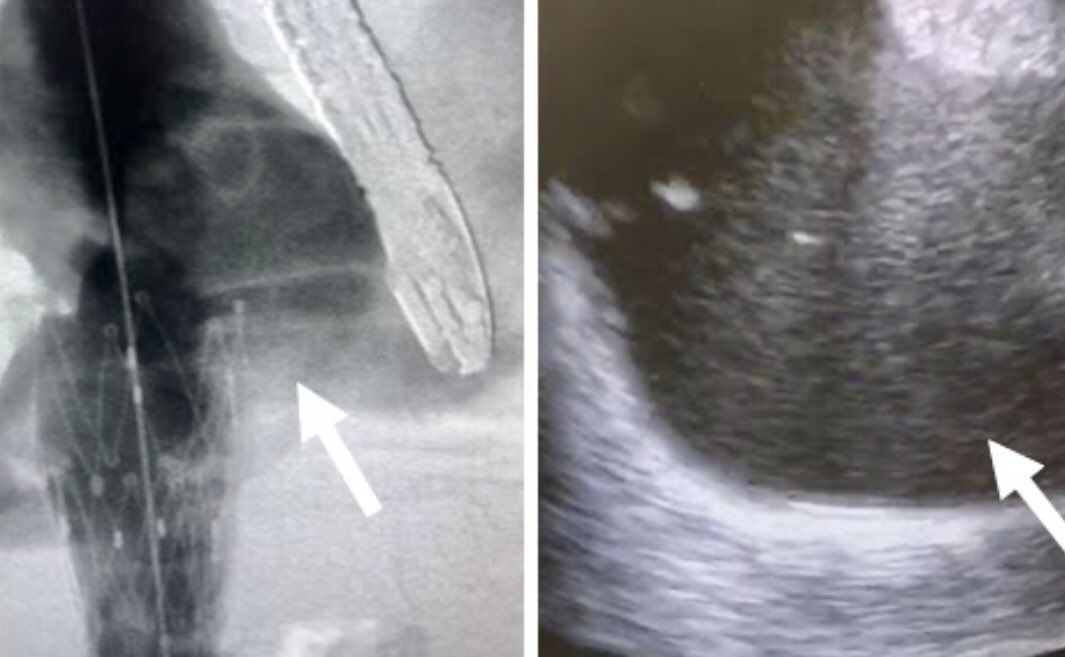

Pt presented to ED with CP, SOB. CXR shows embolized venous stent from OSH. Retrieved with 3 snares, 4 forceps, OR on standby,

@UABVascular help, 26F sheath, extra IR. Immediate symptom relief@SIRspecialists@SIRRFS@JVIRmedia#withoutascalpel#MIIPS#venous#embolize@uab_irpic.twitter.com/WpoUEt3P7z